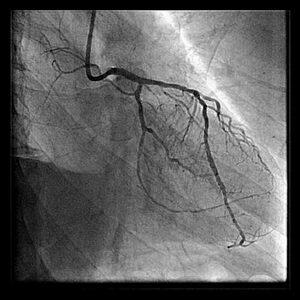

画像のPCI-1、2、3は1stPCIで1年後のAMI、resque後、stenting後となっています。

resqueでは血栓が引けたように記憶しています。